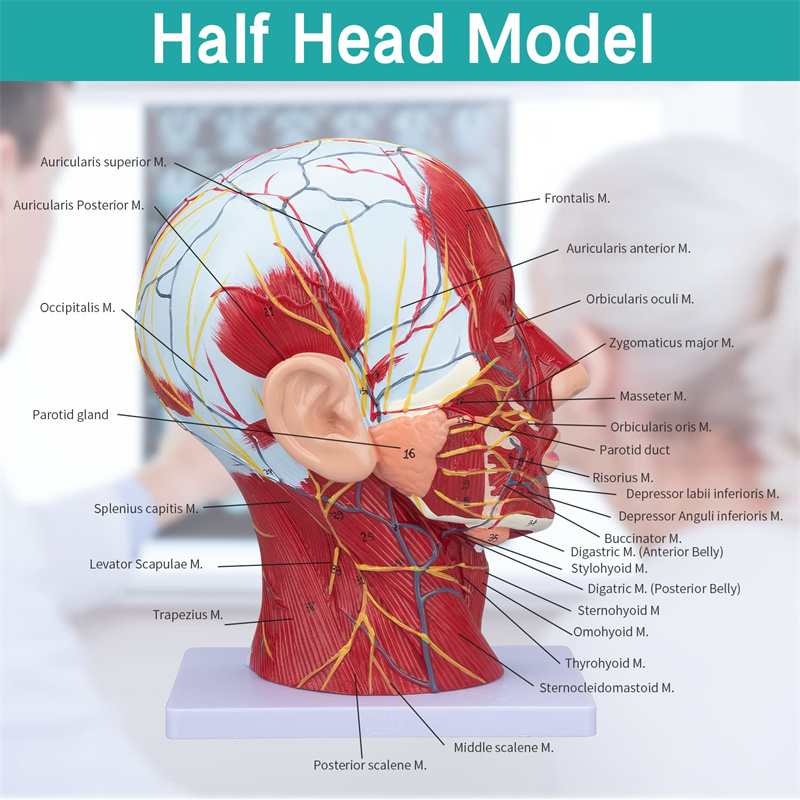

【Model de mușchi neurovascular superficial】 extrem de detaliat, numere marcate, detașabile, adânciți înțelegerea mușchilor superficiali, vaselor, nervilor și structurilor interne ale capului și gâtului. Red-Artery, vene albastru, galben-port.

【Caracteristici】 arată mușchii superficiali ai feței expuse; vasele de sânge superficiale și nervii feței & scalp; structurile interioare ale glandei parotide și ale tractului respirator superior; Structura de secțiune sagitală a coloanei vertebrale cervicale.

Acest model arată detalii despre gâtul dreptului drept și secțiunea sagitală mijlocie a omului. inclusiv superficialul

mușchii feței expuse; vasele de sânge superficiale și nervii feței și ale scalpului; Structurile interioare

a glandei parotide și a tractului respirator superior; Structura de secțiune sagitală a coloanei vertebrale cervicale.

Modelul a arătat morfologia locală a secțiunilor sagitale mediale și laterale ale capului și gâtului și ale structurilor sale vasculare și nervoase, cu un total de 100 de indicatori de sit.

Acest model este un model natural de mușchi neurovascular superficial al capului și gâtului, 1 componentă, care arată detaliile capului drept și gâtului drept și secțiunea sagitală mediană, inclusiv mușchii superficiali expuși ai feței, vasele superficiale ale feței și scalpului, nervii și structura medială a glandei parotide și a tractului respirator superior și a structurii secțiunii sagitale a coloanei vertebrale cervicale